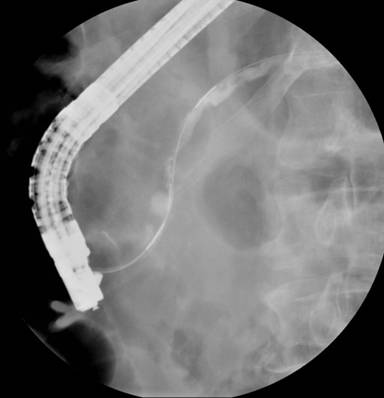

After fulguration of the stone, the basket and stone fragments were easily removed by applying gentle traction on the wires outside the patient’s mouth (Figure 3).

|

Figure 3. Relief of impacted basket after laser lithotripsy. |